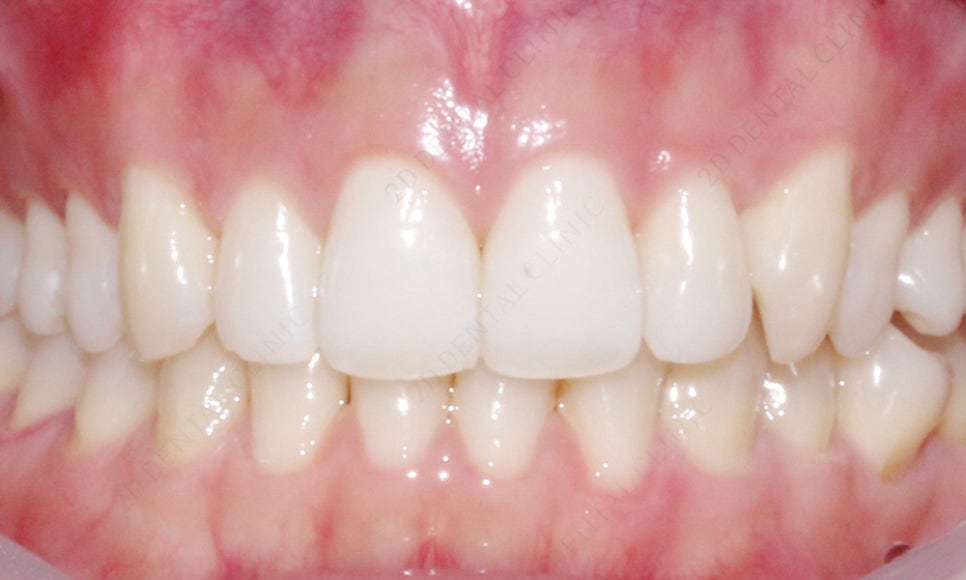

2D치과(투디치과) 앞니교정 기간 [4개월 소요]

회전이 되어있던 측절치가 제자리로

개선이 완료 되었어요.

환자분께서 신경이 쓰이셨던

덧니 같은 느낌의 치아도 사라지고 자신 있게

웃을 수 있다며 많이 좋아하셨답니다